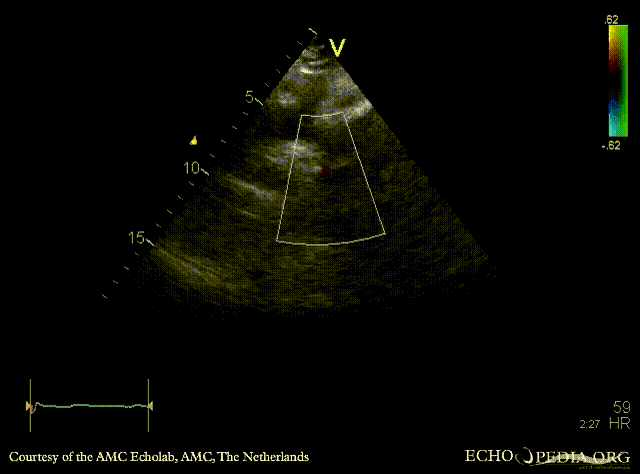

| Suprasternal view, Color Doppler in a patient with coarctatio aortae | Continuous-wave doppler: high velocity flow in descending aorta, sawtooth phenomenon |